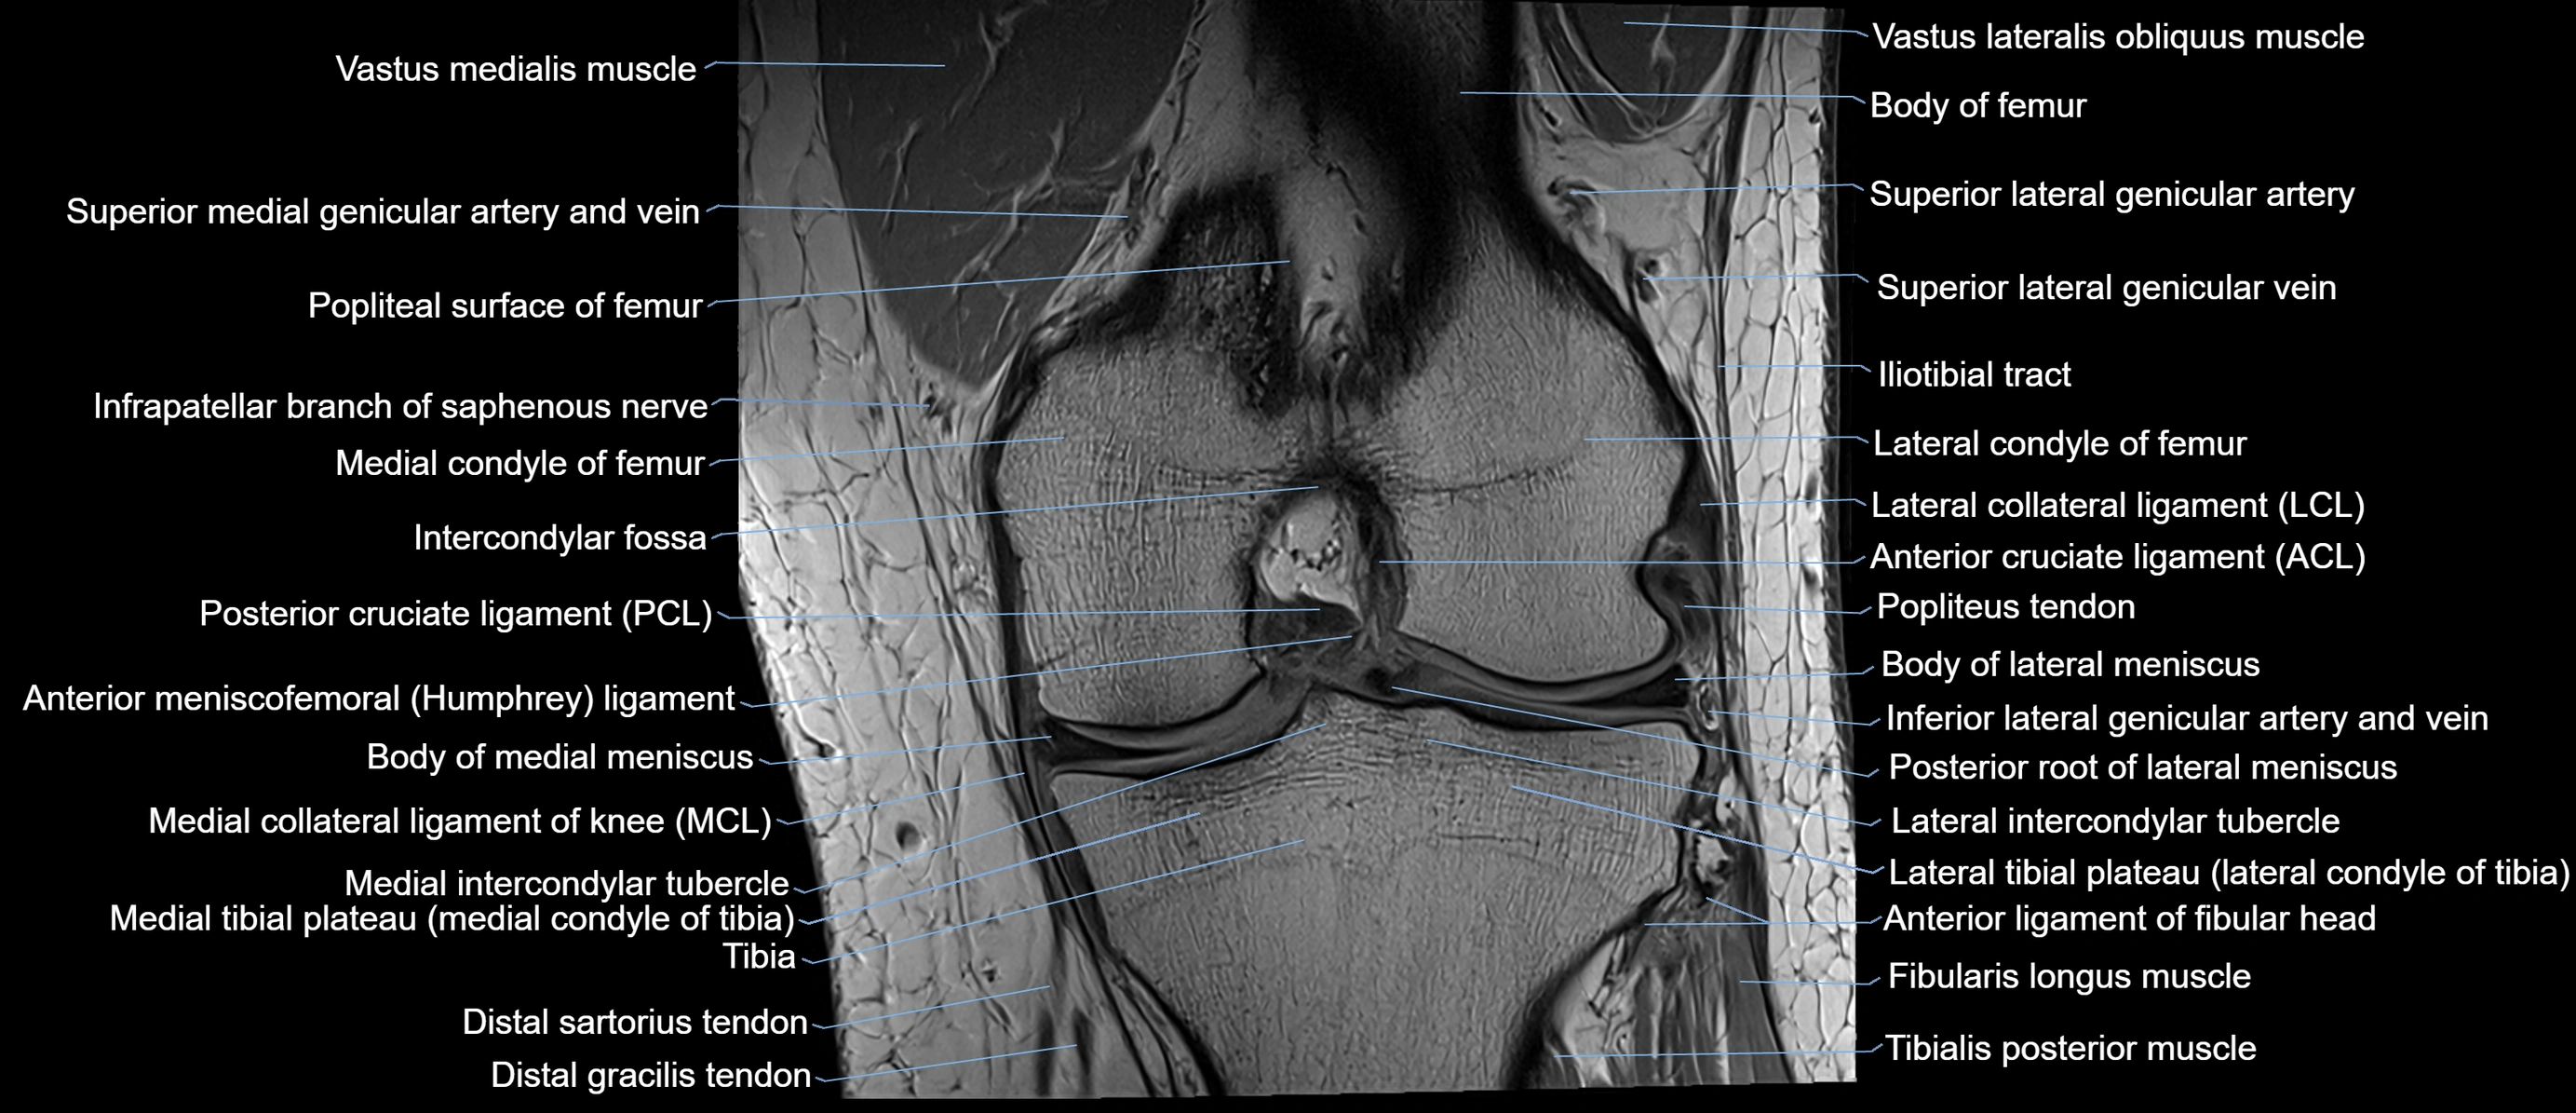

- Anterior cruciate ligament

- Anterior horn of lateral meniscus

- Anterior ligament of fibular head

- Anterior meniscofemoral ligament

- Body of lateral meniscus

- Body of medial meniscus

- Inferior lateral genicular artery

- Inferior lateral genicular vein

- Infrapatellar branch of saphenous nerve

- Intercondylar fossa

- Lateral collateral ligament

- Lateral condyle of femur

- Lateral intercondylar tubercle

- Lateral meniscus

- Lateral tibial plateau

- Medial collateral ligament

- Medial condyle of femur

- Medial condyle of tibia

- Medial intercondylar tubercle

- Medial meniscus

- Medial tibial plateau

- Posterior cruciate ligament

- Posterior root of lateral meniscus

- Superior lateral genicular artery

- Superior lateral genicular vein

- Vastus Lateralis Obliquus Muscle

- Vastus lateralis muscle

- Vastus medialis muscle